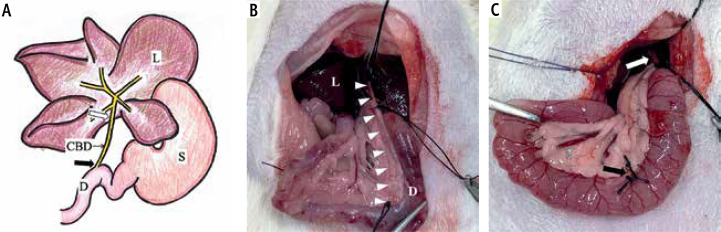

Material and methods: We produced a rat model of extrahepatic biliary obstruction (group O, n = 9) and compared the stools from these rats with those of control group rats (group C, n = 6) by a fluorescence technique. ICG was administered (0.5 mg/kg) through the caudal vein; group O received ICG at the end of surgery.